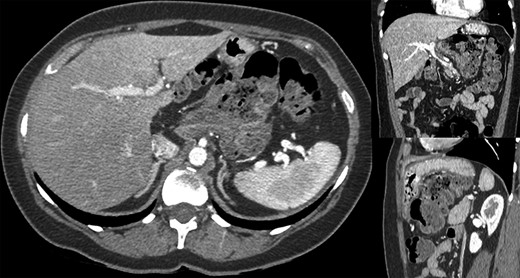

A 44-year-old female patient, without prior abdominal surgery, was admitted to the emergency department with an acute epigastric abdominal pain, without nausea. She presented similar episodes of pain in the past, without having ever requested a medical opinion. Physical examination revealed an acute epigastric pain without signs of peritonitis. Laboratory analyses were within normal limits. A computed tomography showed an internal hernia of the colon in the lesser sac, going back from the liver pedicle (Fig. 1). There were neither occlusion nor ischemia. We performed immediately a diagnostic laparoscopy with one 11-mm umbilical port and two 5-mm ports (one in the left lumbar and one in the hypogastrium). Exploration confirmed that the ascending colon and the right colonic flexure had herniated through the foramen of Winslow (Fig. 2). The colon was reduced with an atraumatic Johann’s graspers and was viable, cecum, ascending colon and the right colonic flexure was mobile due to a misapposition of the right Told fascia. To prevent recurrent herniation we performed the fixation to the lateral wall of the cecum, ascending colon and right colonic flexure with several non-absorbable sutures (Fig. 3). We did not perform the closure of the Winslow’s hiatus. Postoperatively, the patient recovery was uneventful and was discharged home 2 days later. A computed tomography was performed 1 month later for another reason, showing a good result of the right colon fixation on the lateral wall (Fig. 4). Twenty months after surgery, the patient totally recovered and has not experienced any recurrence or occlusion.

Fixation to the lateral wall of the ascending colon with several non-absorbable sutures.